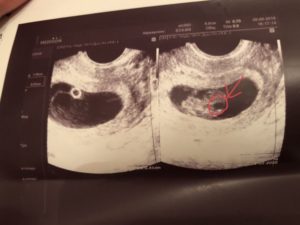

- УЗИ, определяет 8 недель беременности размер плода, состояние кровоснабжения, плаценты и т.д.;